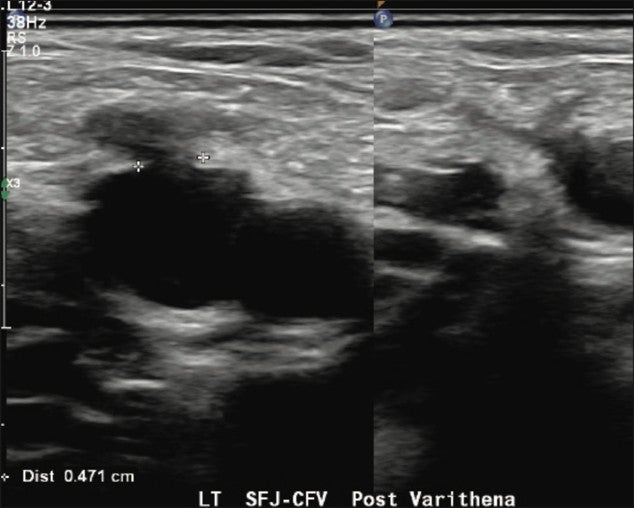

Immediately after the procedure, successful venospasm of the treated varicosities and residual GSV were documented with duplex and grayscale imaging. A final ultrasound image was obtained to confirm a patent and compressible left common femoral vein Saphenofemoral Junction (SFJ).

Figure 4. Patent and compressible left CFV/SFJ post Varithena treatment.